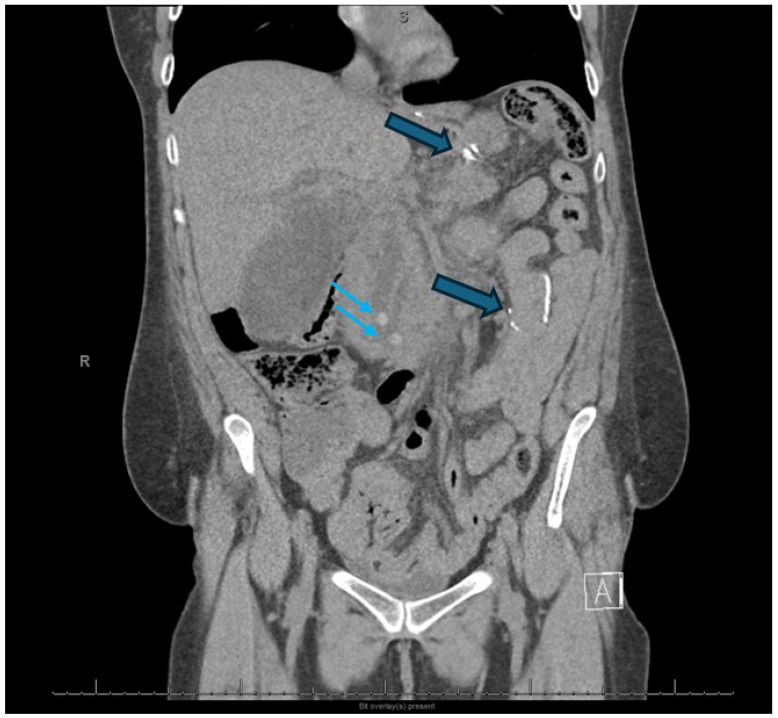

在美国,急性胰腺炎(AP)是胃肠道相关住院治疗的最常见原因,其中胆结石疾病和酒精是主要病因。治疗取决于疾病的严重程度,分为间质性水肿性胰腺炎或坏死性胰腺炎,严重程度根据局部并发症和全身器官功能障碍进一步分层。无论病因如何,初始治疗包括积极的乳酸林格氏液静脉液体复苏、疼痛和恶心控制、24至48小时内早期口服喂养,并在必要时进行病因指导干预。在胆源性胰腺炎中,当伴有胆管炎或持续性胆道梗阻时,早期内镜逆行胆管造影(ERCP)联合括约肌切开术,随后腹腔镜胆囊切除术作为结石清除的标准护理。在急性期,介入治疗在无并发症AP中的作用有限,除了胆道减压或鼻空肠管置入的肠内喂养支持。然而,在伴有并发症的严重AP中,介入放射学(IR)和内镜入路起着关键作用。IR有助于早期经皮引流有症状的急性积液和感染坏死,特别是在非内窥镜可及的腹膜后积液或依赖积液中,通过逐步入路改善结果。红外引导血管造影栓塞是出血并发症的首选方式,包括假性动脉瘤。在延迟期,壁闭塞性坏死(WON)和胰腺假性囊肿采用超声内镜(EUS)引导引流治疗,直接内镜下坏死切除术(DEN)用于感染坏死。双模引流(DMD),结合经皮和内镜引流,越来越多地用于广泛或复杂的集合,反映了胃肠病学和介入放射学之间的合作努力,类似于在进行视频辅助腹膜后清创(VARD)的机构中存在的IR和外科之间的合作。胰周积液可能瘘入邻近的结构,包括胃、小肠或结肠,需要经毛细血管支架置入,或不需要用镜外夹(OTSC)或缝合装置额外封闭肠道渗漏。此外,胰管断裂的内镜下处理与经毛细血管或经壁支架置入在胰管断裂综合征(DPDS)的病例中起着关键作用。各种介入技术(包括腹膜后、腹腔镜、开放手术和内镜引流)的比较结果强调了向微创入路的转变,降低了发病率和住院时间。内窥镜和介入放射引导技术的整合已经改变了AP并发症的管理,多学科合作对于获得最佳患者结果至关重要。

Acute pancreatitis (AP) is the most common cause of gastrointestinal-related hospitalizations in the United States, with gallstone disease and alcohol as the leading etiologies. Management is determined by disease severity, classified as interstitial edematous pancreatitis or necrotizing pancreatitis, with severity further stratified based on local complications and systemic organ dysfunction. Regardless of etiology, initial treatment involves aggressive intravenous fluid resuscitation with Lactated Ringer's solution, pain and nausea control, early oral feeding in 24 to 48 h, and etiology-directed interventions when indicated. In gallstone pancreatitis, early endoscopic retrograde cholangiopancreatography (ERCP) with sphincterotomy is indicated in the presence of concomitant cholangitis or persistent biliary obstruction, with subsequent laparoscopic cholecystectomy as standard of care for stone clearance. The role of interventional therapy in uncomplicated AP is limited in the acute phase, except for biliary decompression or enteral feeding support with nasojejunal tube placement. However, in severe AP with complications, interventional radiology (IR) and endoscopic approaches play a pivotal role. IR facilitates early percutaneous drainage of symptomatic, acute fluid collections and infected necrosis, particularly in non-endoscopically accessible retroperitoneal or dependent collections, improving outcomes with a step-up approach. IR-guided angiographic embolization is the preferred modality for hemorrhagic complications, including pseudoaneurysms. In the delayed phase, walled-off necrosis (WON) and pancreatic pseudocysts are managed with endoscopic ultrasound (EUS)-guided drainage, with direct endoscopic necrosectomy (DEN) reserved for infected necrosis. Dual-modality drainage (DMD), combining percutaneous and endoscopic drainage, is increasingly utilized in extensive or complex collections, reflecting a collaborative effort between gastroenterology and interventional radiology comparable to that which exists between IR and surgery in institutions that perform video assisted retroperitoneal debridement (VARD). Peripancreatic fluid collections may fistulize into adjacent structures, including the stomach, small intestine, or colon, requiring transpapillary stenting with or without additional closure of the gut leak with over-the-scope clips (OTSC) or suturing devices. Additionally, endoscopic management of pancreatic duct disruptions with transpapillary or transmural stenting plays a key role in cases of disconnected pancreatic duct syndrome (DPDS). Comparative outcomes across interventional techniques-including retroperitoneal, laparoscopic, open surgery, and endoscopic drainage-highlight a shift toward minimally invasive approaches, with decreased morbidity and reduced hospital stay. The integration of endoscopic and interventional radiology-guided techniques has transformed the management of AP complications and multidisciplinary collaboration is essential for optimal patient outcomes.